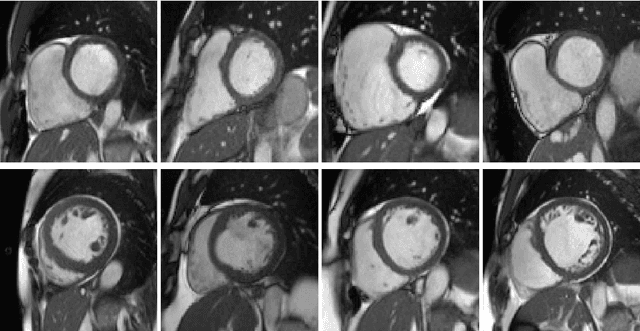

Abstract:Convolutional neural network (CNN) based segmentation methods provide an efficient and automated way for clinicians to assess the structure and function of the heart in cardiac MR images. While CNNs can generally perform the segmentation tasks with high accuracy when training and test images come from the same domain (e.g. same scanner or site), their performance often degrades dramatically on images from different scanners or clinical sites. We propose a simple yet effective way for improving the network generalization ability by carefully designing data normalization and augmentation strategies to accommodate common scenarios in multi-site, multi-scanner clinical imaging data sets. We demonstrate that a neural network trained on a single-site single-scanner dataset from the UK Biobank can be successfully applied to segmenting cardiac MR images across different sites and different scanners without substantial loss of accuracy. Specifically, the method was trained on a large set of 3,975 subjects from the UK Biobank. It was then directly tested on 600 different subjects from the UK Biobank for intra-domain testing and two other sets for cross-domain testing: the ACDC dataset (100 subjects, 1 site, 2 scanners) and the BSCMR-AS dataset (599 subjects, 6 sites, 9 scanners). The proposed method produces promising segmentation results on the UK Biobank test set which are comparable to previously reported values in the literature, while also performing well on cross-domain test sets, achieving a mean Dice metric of 0.90 for the left ventricle, 0.81 for the myocardium and 0.82 for the right ventricle on the ACDC dataset; and 0.89 for the left ventricle, 0.83 for the myocardium on the BSCMR-AS dataset. The proposed method offers a potential solution to improve CNN-based model generalizability for the cross-scanner and cross-site cardiac MR image segmentation task.

Abstract:Cardiovascular magnetic resonance (CMR) imaging is a standard imaging modality for assessing cardiovascular diseases (CVDs), the leading cause of death globally. CMR enables accurate quantification of the cardiac chamber volume, ejection fraction and myocardial mass, providing information for diagnosis and monitoring of CVDs. However, for years, clinicians have been relying on manual approaches for CMR image analysis, which is time consuming and prone to subjective errors. It is a major clinical challenge to automatically derive quantitative and clinically relevant information from CMR images. Deep neural networks have shown a great potential in image pattern recognition and segmentation for a variety of tasks. Here we demonstrate an automated analysis method for CMR images, which is based on a fully convolutional network (FCN). The network is trained and evaluated on a large-scale dataset from the UK Biobank, consisting of 4,875 subjects with 93,500 pixelwise annotated images. The performance of the method has been evaluated using a number of technical metrics, including the Dice metric, mean contour distance and Hausdorff distance, as well as clinically relevant measures, including left ventricle (LV) end-diastolic volume (LVEDV) and end-systolic volume (LVESV), LV mass (LVM); right ventricle (RV) end-diastolic volume (RVEDV) and end-systolic volume (RVESV). By combining FCN with a large-scale annotated dataset, the proposed automated method achieves a high performance on par with human experts in segmenting the LV and RV on short-axis CMR images and the left atrium (LA) and right atrium (RA) on long-axis CMR images.